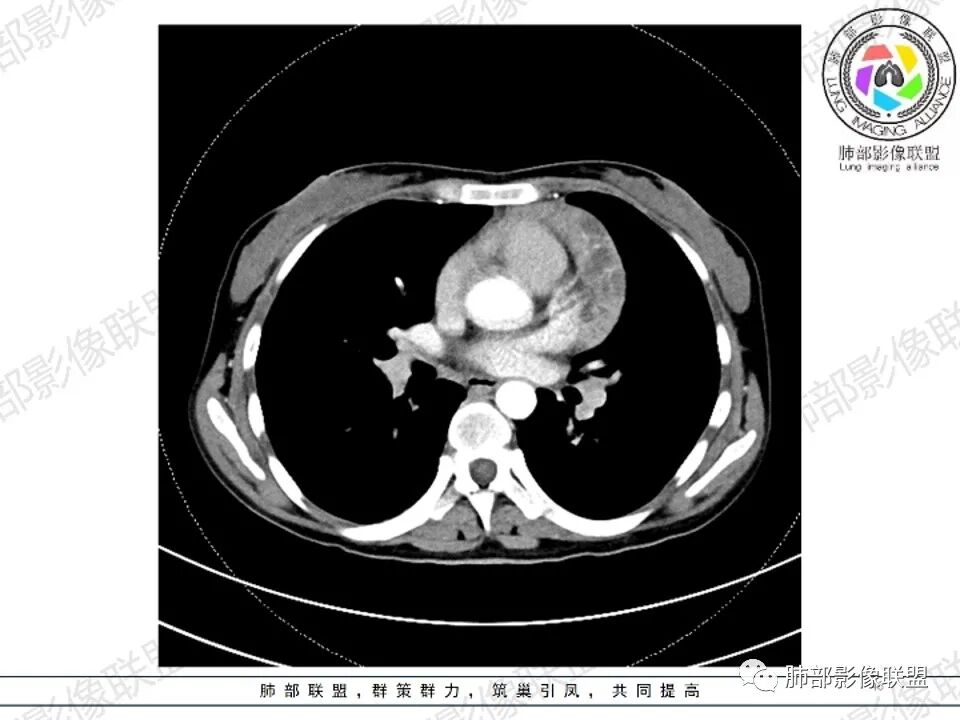

女,27,间断头晕、乏力3年,左眼视物模糊2月。贫血。胸部CT:前纵隔不规则肿块,多结节融合,边界不清,沿主动脉及肺动脉间隙生长,平扫密度欠均匀,增强扫描可见多发低密度坏死,纵隔血管供血穿行,腋窝多发大小不等淋巴结肿大。考虑恶性病变,胸腺癌?肉瘤?淋巴瘤?鉴别胸腺瘤、结节病等。

临床:年轻女性,慢性病程,多系统病变,头晕,贫血,视物模糊。

CT:定位纵膈病变,前中纵隔多发肿块,质软,塑形,密度不均匀,边界清楚。增强不均匀强化,坏死边界清楚,血管漂浮征。双侧腋下多组淋巴结肿大,明显异常强化。

考虑淋巴瘤可能。

2.影像显示前纵隔不规则块状影,依势贴附心脏大血管旁,密度不均,边界不甚清楚,有结节融合感。

3.病灶轻度不均匀强化,可见血管穿行,散在液性低密度区。

双肺门未见肿大淋巴结。

4.双侧腋窝区见增大淋巴结,边界清楚。

1.年轻女性,前纵隔不规则块状影,密度不均,边界不甚清楚,有结节融合感,轻度不均匀强化,可见血管穿行,最常见最符合的无疑是淋巴瘤!